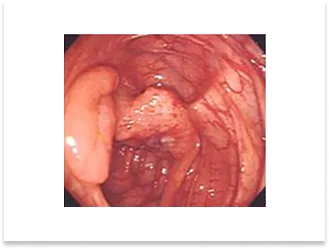

胃体中部の隆起型進行癌症例

術前内視鏡写真